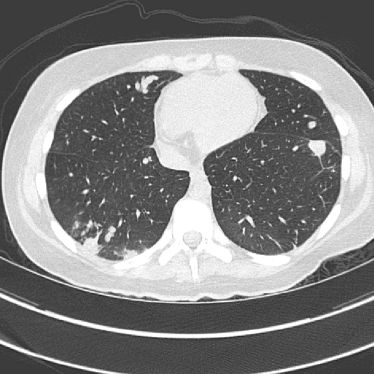

To evaluate image quality, we first tested the performance of JENG on a standard CT phantom, CT ACR 464 phantom 35. Then we tested JENG on 5 clinical thoracic datasets and 3 abdominal datasets. The ACR 464 phantom contains four modules in total, with each module 40 mm in depth and 200 mm in diameter. The first module has 4 different inserts to test CT number fidelity. In addition, the module contains a series of wires for cross-plane resolution evaluation, shown as white horizontal bars near the center in Fig. 9(a), and are visible in 0.5 mm z-axis increments. The second module tests low contrast resolution, but is not used in this paper. The third module, shown in Fig. 9(b), is a uniform cylinder of water-equivalent material of 0 Hounsfield units (HU), and we used this module to quantitatively measure image noise profile and in-plane resolution. The fourth module consists of resolution bars of various spatial frequencies for analysis on high contrast resolution. To scan the phantom, the scanner setup used dual sources with 2 focal spots at each source. In addition, the projections were acquired using the same protocol for clinical thoracic scans with 100 KV, a nominal tube current of 718 mA and a high helical pitch of 2.8. For all experiments, we compared JENG against the state-of-the-art Siemens ADMIRE, reconstructed with a BL-64 soft tissue sharp kernel, and we define ADMIRE as the clinical standard hybrid IR method for the rest of the paper.

Refer to caption(a) Clinical Standard IRRefer to caption(a) Clinical Standard IR

Refer to caption(b) JENGRefer to caption(b) JENG

Refer to caption(c) Clinical Standard IRRefer to caption(c) Clinical Standard IR

Refer to caption(d) JENGRefer to caption(d) JENG

Figure 14: Qualitative clinical results from a thoracic CT staging dataset for a 12-year-old with osteosarcoma with pulmonary metastases. The clinical standard hybrid IR is shown on the left and JENG is on the right. (a) The clinical standard hybrid IR in lung window with a window center of -600 HU and a window width of 1500 HU. (b) JENG at a resolution comparable to the clinical standard, but with less noise and fewer artifacts. (c) The clinical standard hybrid IR in soft tissue window with a window center of 55 HU and a window width of 440 HU. A metastatic lung cancer nodule can be found in the left upper lobe. (d) JENG in soft tissue window at a comparable resolution, but with less noise and fewer artifacts. Note that JENG is not fully corrected for beam hardening artifacts.